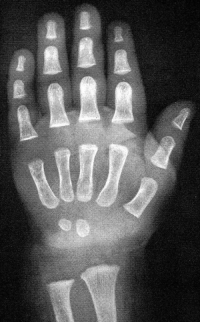

Sexo Feminino

Recém-Nascido

Fonte: GREULICH, W.W. & PYLE, S.I.: Radiografic Atlas of Development of the Hand and Wrist. Stanford University Press, 2° edition, 1959.